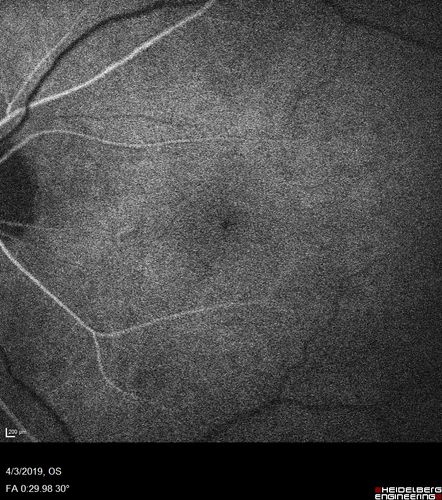

Stellate Non-heredtiary Idiopathic Foveomacular Retinoschisis (SNIFR)

77 year old man who is healthy and 6'6" tall with 20/40 vision and no complaints. OCT shows diffuse retinoschisis.